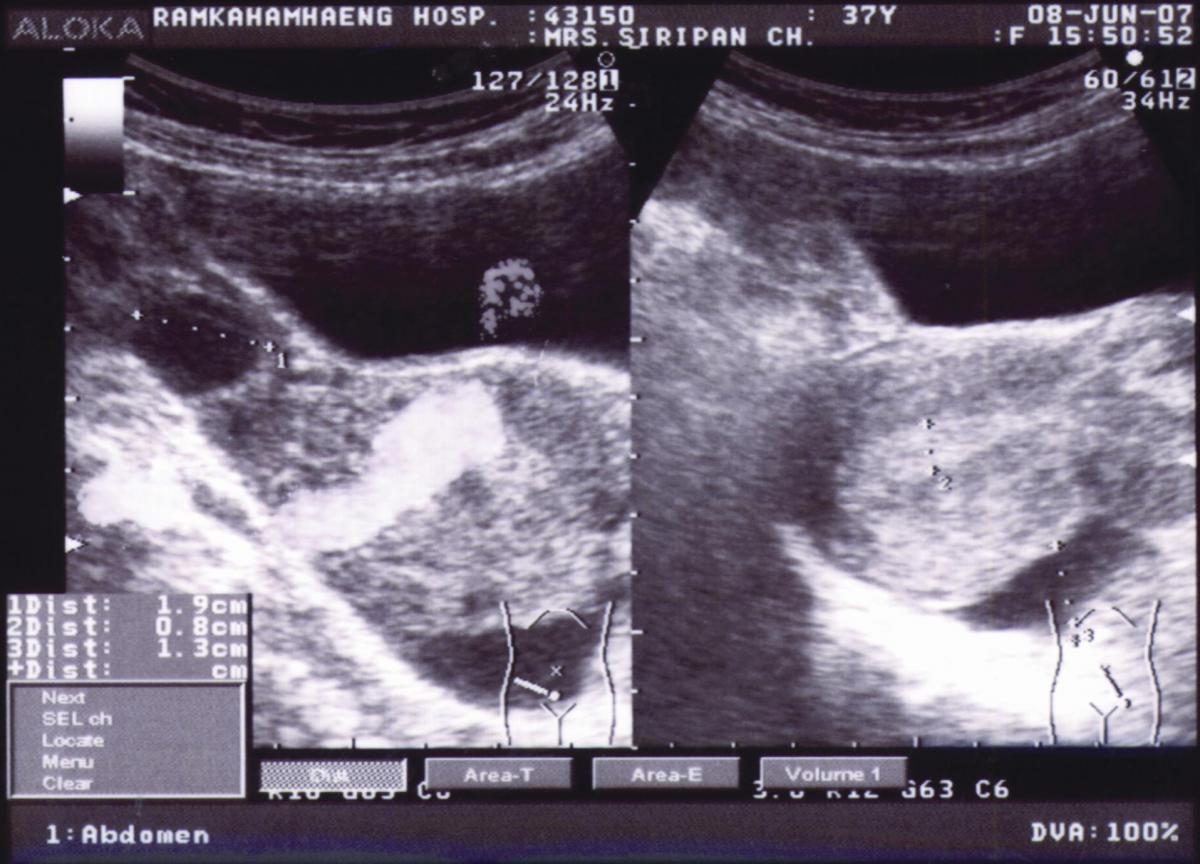

หญิงไทยโสด อายุ 37 ปี รู้สึกปวดท้องน้อยด้านขวา มานาน 1 คืน. ประจำเดือนมาปกติเมื่อ 2 สัปดาห์ที่ผ่านมา. ไม่มีประวัติเพศสัมพันธ์กับใครเลย. ภาพถ่ายทางรังสีปรากฏลักษณะดังภาพที่ 4.

1. Ultrasonogram ของช่องท้องส่วนล่าง.

2. เงามดลูกมีขนาดปกติ แต่บ่งชี้เยื่อบุมดลูกหนาประมาณ 0.8 ซม.และปรากฏเงาของเหลวในช่องเชิงกรานหนาประมาณ 1.3 ซม.

3. การรั่วของถุงน้ำจากรังไข่ของในระยะกลางรอบระดู เนื่องจากมดลูกมีเยื่อบุหนาและมีถุงน้ำรังไข่ช่วงมีน้ำในเชิงกราน ร่วมกับการปวดท้องในช่วงระยะการตกไข่ คือ 14-15 วัน หลังหรือก่อนมีประจำเดือน.